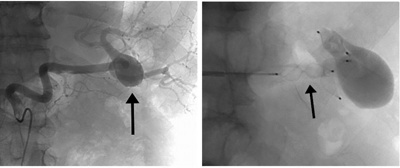

milz-endovaskulär

Minimalinvasive endovaskulärer Ausschaltung eines Milzarterienaneurysmas (A: Pfeil) mittels Vascular Plugs (B: Pfeil).